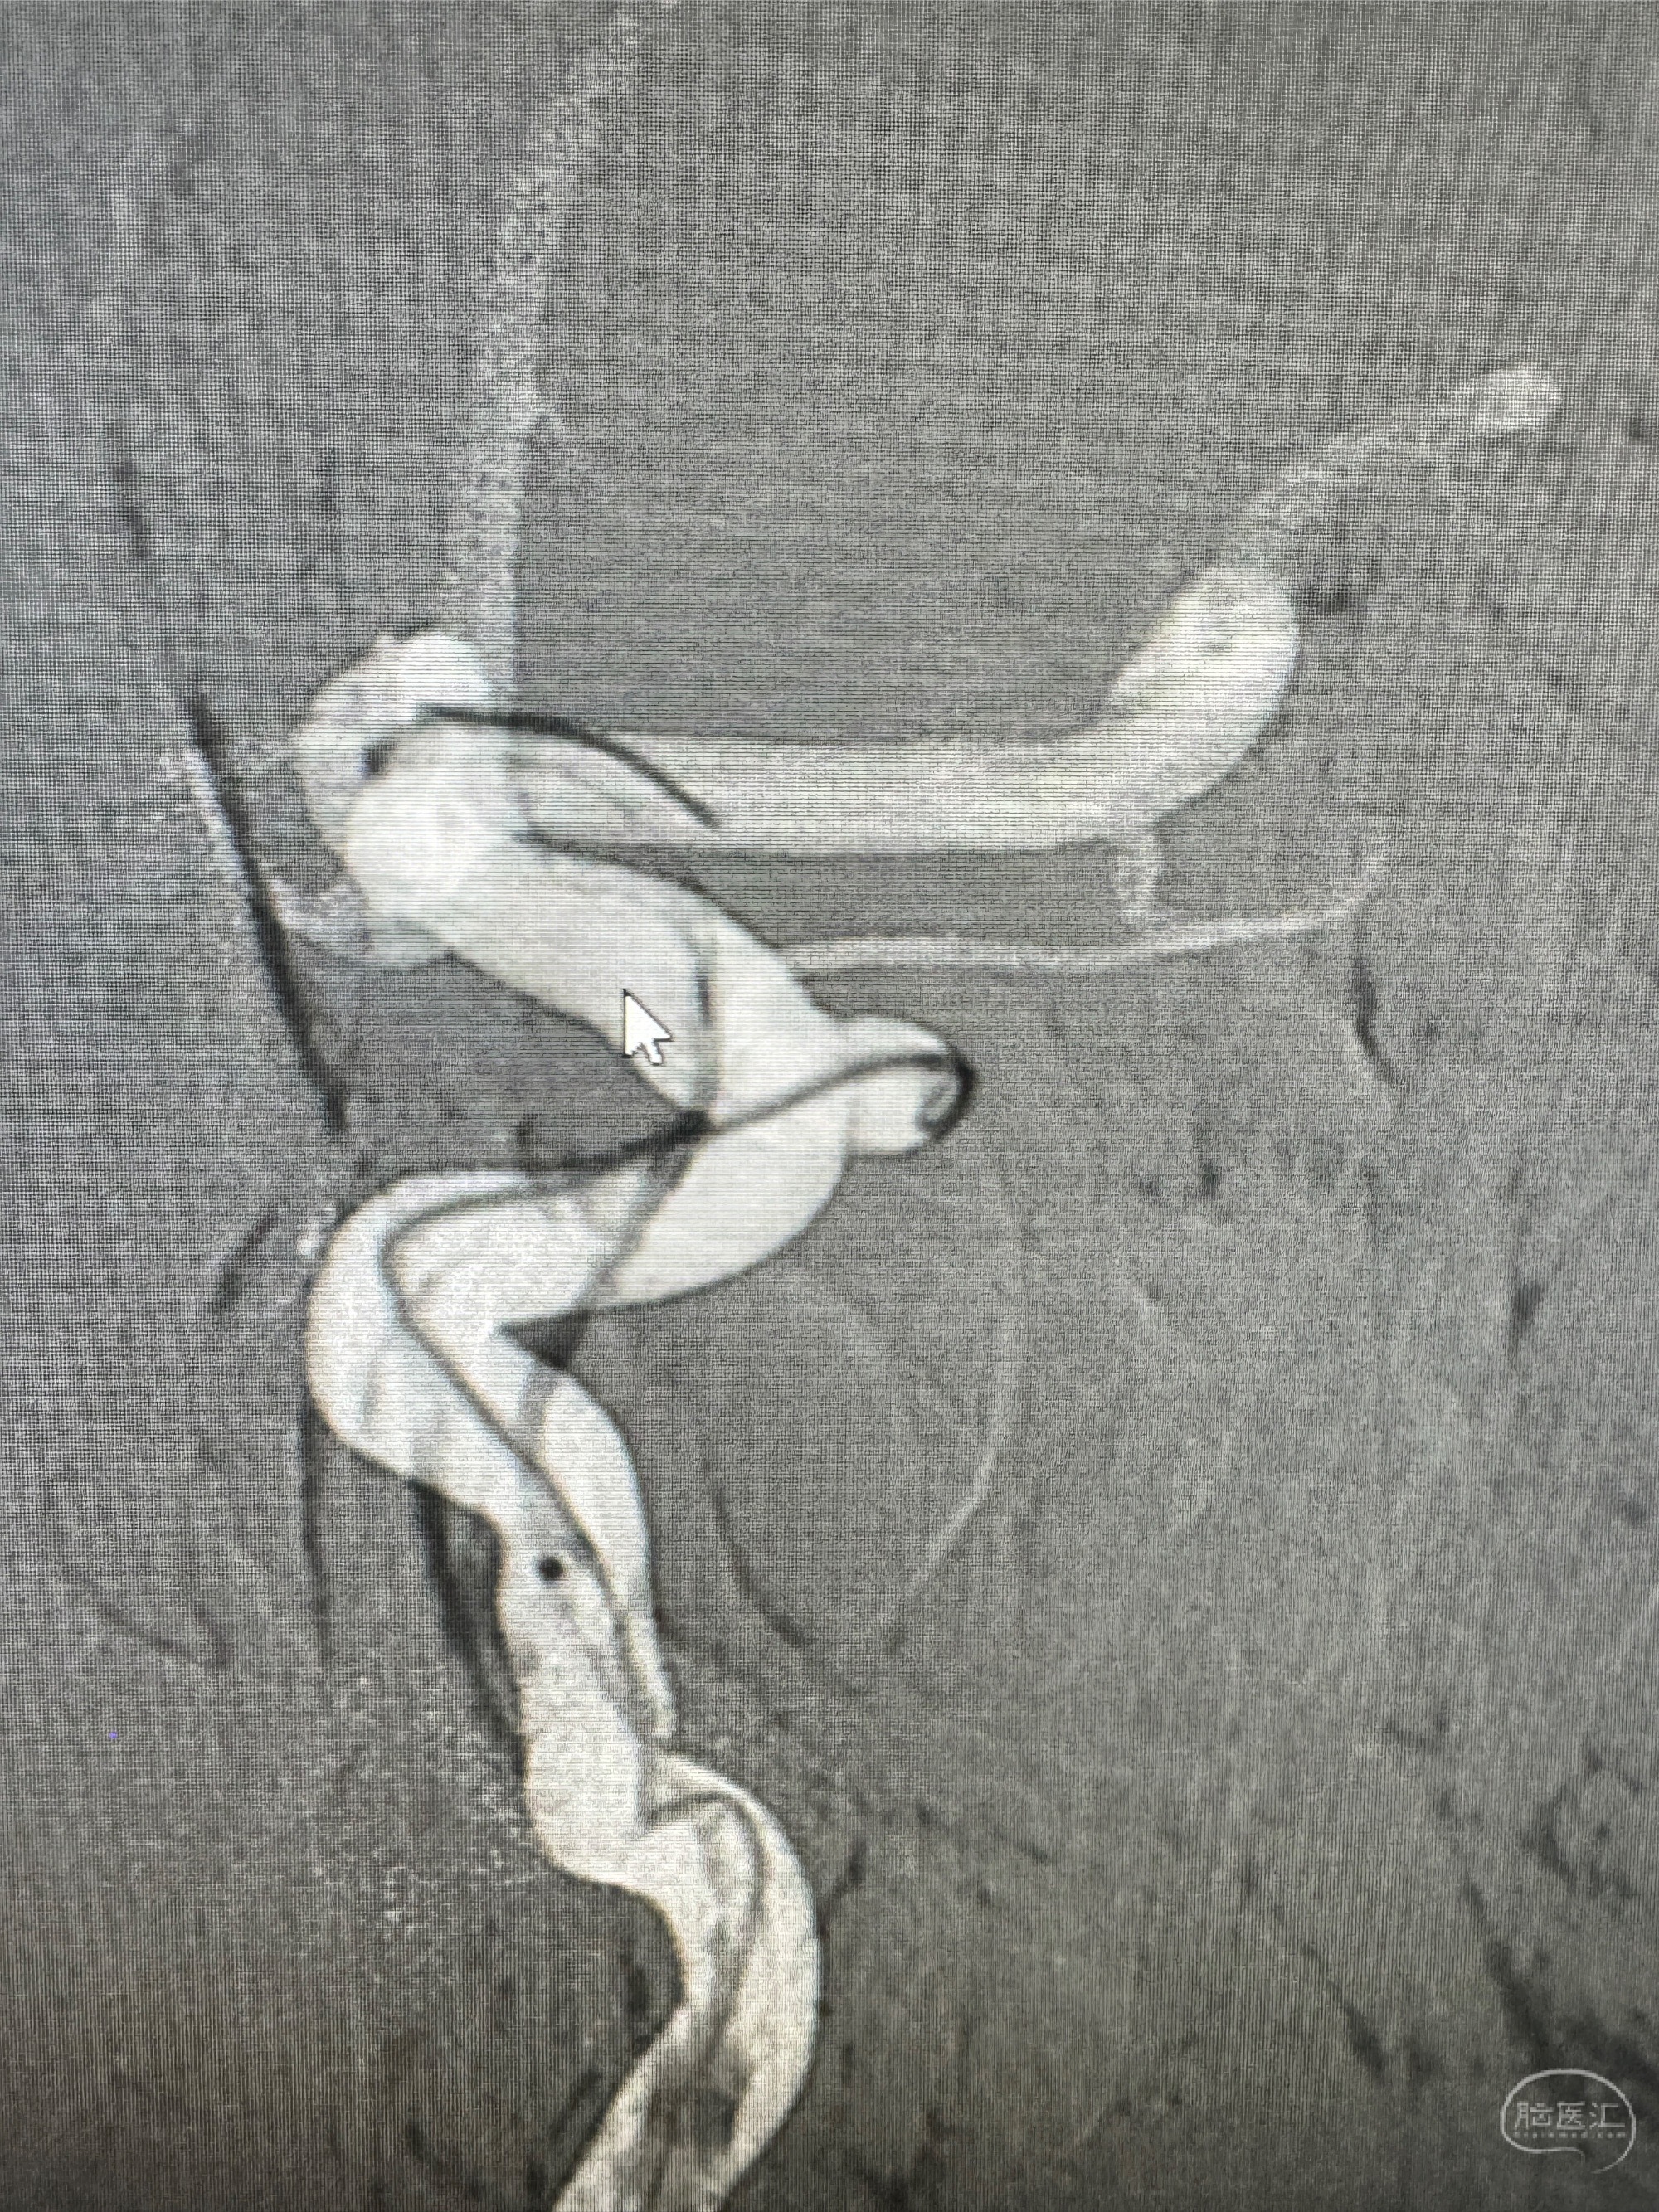

2023.07.24DSA+全麻下颅内动脉瘤密网支架+弹簧圈辅助干预

2023.12.26术后6月复查DSA:动脉瘤痊愈,局部不规则动脉膨出与前相仿

6个月复查显示密网支架内内膜增生,局段不规则动脉膨隆于术后即刻相仿,给予强化降脂:立普妥+依折麦布,6月后再随访